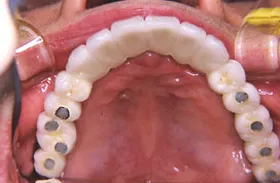

金属を白くし、歯茎の黒ズミを改善したケース

■治療前

■治療後

| 主訴 | 全体的に白い歯にして見た目をきれいにしたい 歯茎が黒くなっているのが気になる、歯ならびも良くしたい |

|---|---|

| 治療方法 | 矯正治療+歯茎の黒ずみの改善+補綴治療 |

| 治療期間 | 3年 |

| 通院回数等 | 約40回 |

| 費用 | 約350万円 |

| リスク・副作用 | 矯正治療も行ったので治療期間が長くなった |